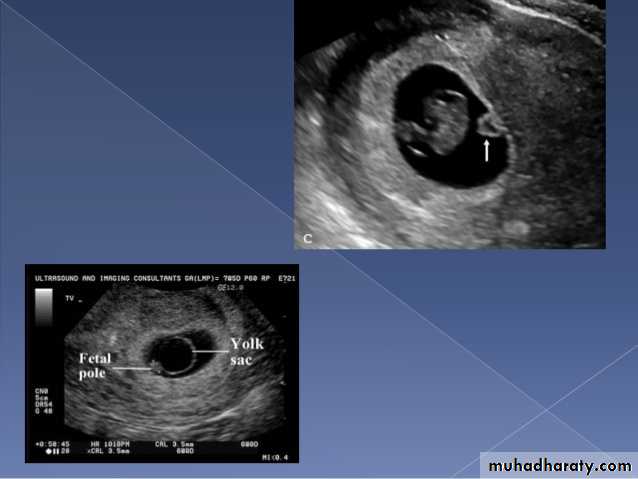

Anembryonic pregnancy is a form of a failed early pregnancy, where a gestational sac develops, but the embryo does not form. The term blighted ovum is synonymous with this, but is falling out of favour and is best avoided.Radiographic features

Ultrasound

An anembryonic pregnancy may be diagnosed when there is no fetal pole identified on endovaginal scanning , and:the size of the gestational sac is such that a fetal pole should be seen: MSD ≥25 mm on TVS (by RCOG criteria)